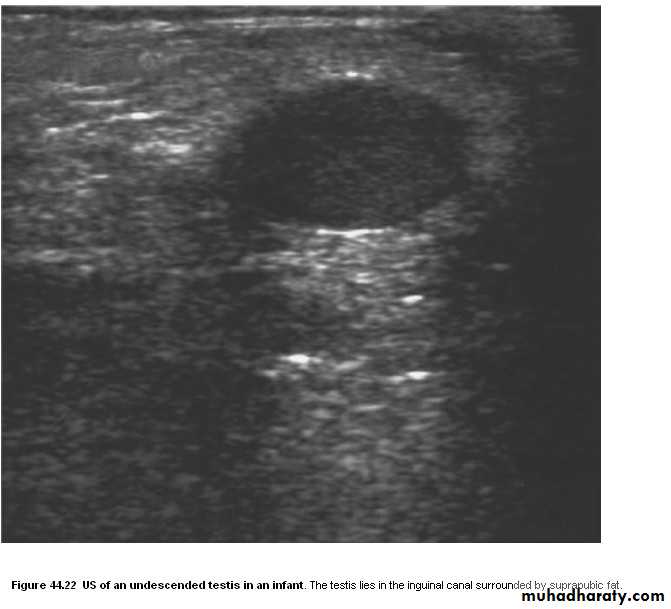

• Ectopic testis in the inguinal canal can be diagnosed by US. When the ectopic testis lies within the abdomen, or where the US is inconclusive, MRI is the investigation of choice.